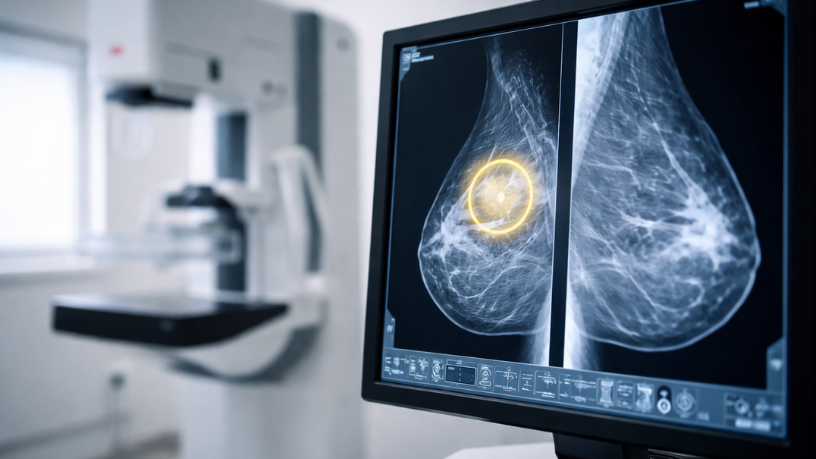

A mamografia é um exame de imagem desenvolvido para analisar detalhadamente o tecido mamário. Conforme explica Vinicius Tadeu Sattin Rodrigues, esse método utiliza tecnologia capaz de captar imagens das estruturas internas das mamas com grande precisão. Dessa forma, torna-se possível identificar pequenas alterações que ainda não provocam sintomas perceptíveis.

Essas alterações podem incluir nódulos muito pequenos ou pequenas calcificações que não seriam percebidas em um exame físico. Em muitos casos, essas estruturas são detectadas apenas porque o exame permite visualizar o interior do tecido mamário com maior detalhamento. Assim, o rastreamento por imagem amplia a capacidade de investigação médica.